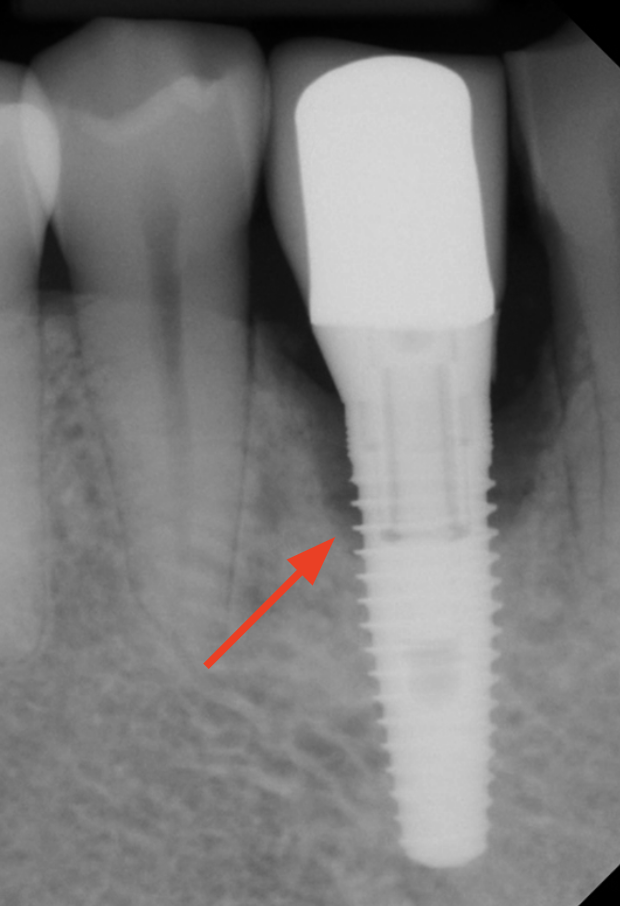

Laser for Periimplantitis

*Follow-up x-rays 9-12 months after treatment